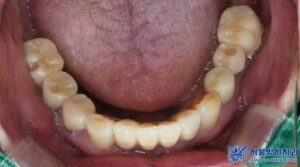

환자분께서는 최종 보철을 장착한 후,

음식을 씹는 느낌도 자연스럽고

앞니가 예쁘게 만들어져 매우

만족스럽다고 하셨으며,

처음 내원하셨을 때와 비교하면

얼굴 표정도 한결 밝아지셨습니다.